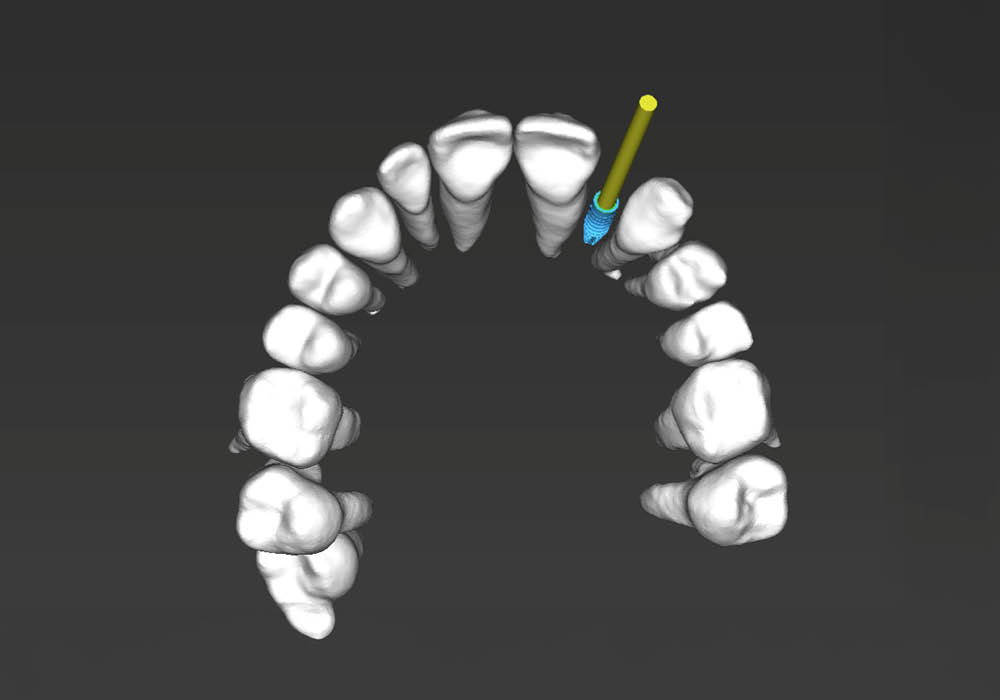

La pianificazione chirurgica ha previsto un’analisi tridimensionale dettagliata del sito implantare, valutato sia da angolazioni multiple sia in visione frontale diretta.

L’obiettivo era quello di definire con precisione posizione, profondità e inclinazione dell’impianto, tenendo conto della vicinanza delle radici adiacenti e della necessità di preservare un adeguato spessore vestibolare.

Questa fase ha permesso di anticipare eventuali criticità e assicurare l’inserzione corretta all’interno dei limiti anatomici disponibili.